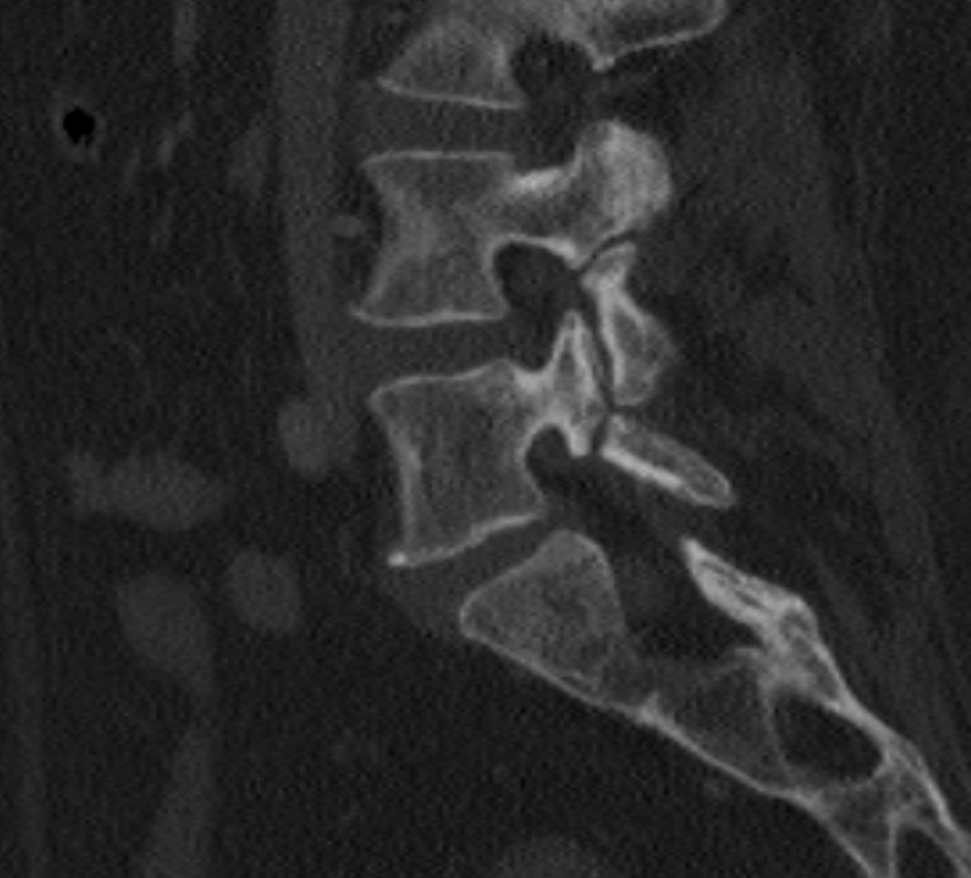

Pars Interarticularis defects